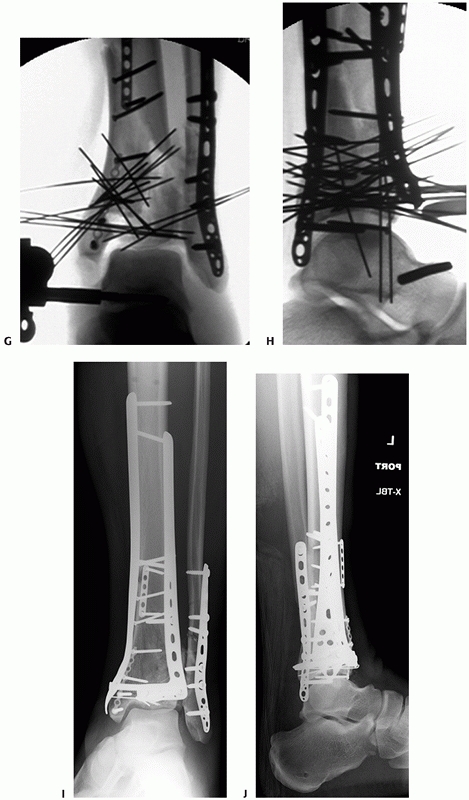

FIGURE 56-13 Injury anteroposterior (A) and lateral (B)

radiographs of a 32-year-old man involved in a moderate speed motor vehicle collision. The lateral radiograph demonstrates marked displacement of the posterolateral fragment from the distal tibia (C,D). Although markedly improved after fibular reduction via a posterolateral incision, substantial residual displacement of the posterolateral articular surface (*) remains. The white arrow denotes an impacted central plafond fragment. Provisional (E) and definitive (F) fixation of the posterolateral articular fragment performed using the posterolateral surgical incision. (continues) |

![]() |

FIGURE 56-13 (continued) At the conclusion of fixation, the distal tibia was managed with spanning external fixation (G-I).

After resolution of soft tissue swelling, the remainder of the tibial plafond was reduced and stabilized using a modified anteromedial approach. (continues) |